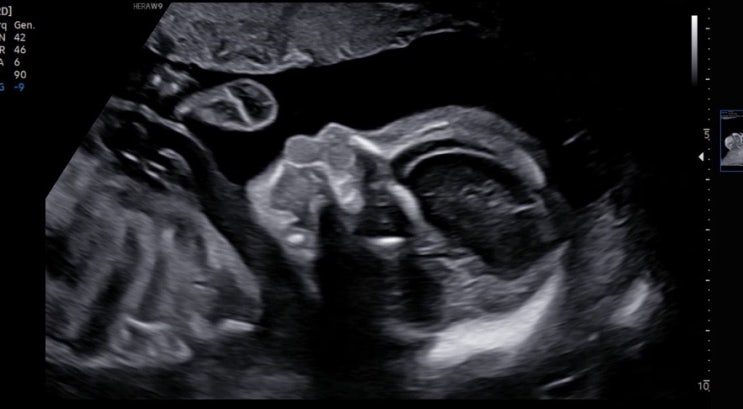

둘째 임신 - 임신 26주 청라여성병원 입체초음파 / 임당검사

드디어 두근대는 입체초음파 날이였어요 사실 임당은 첫째때 없었기에 1도 신경안씀요 ㅋㅋ 아침에 시약을 ...